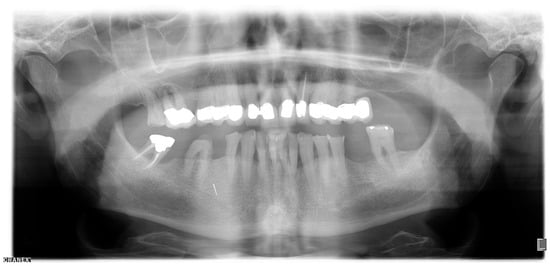

2.1. Orthopantomography (OPT)

Region 45 showed a thin cylindrical, approximately 5 mm (coronal-apical) metallically dense opacity in the OPT (Figure 1).

Figure 1.

Orthopantomogram taken in October 2019.